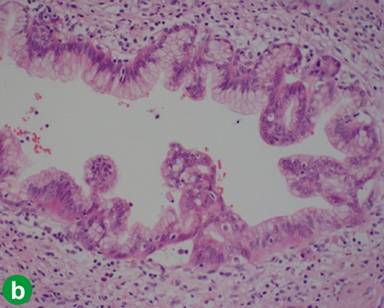

The patient underwent a pylorous preserving pancreaticoduodenectomy and histology confirmed a well differentiated adenocarcinoma arising in the mucosa of ampulla of Vater, with invasion of the seromuscularis externa, soft tissue and perineural space of pancreaticoduodenal sulcus and juxtaduodenal pancreas. Bile duct, duodenal, pancreatic and vascular resection margins, and pancreaticoduodenal lymph nodes were free of tumour. Immunohistochemistry revealed positivity for cytokeratin (CK) 7 and mucin core protein (MUC) 1, and negativity for MUC2 and CK20, appearances consistent with the pancreatobiliary subtype of ampullary carcinoma (Figure 1). Interestingly foci of mucinous metaplasia, of pancreatic duct epithelium corresponding to PanIN-1A, of the pancreatic duct epithelium with patchy chronic pancreatitis and acinar atrophy, were observed at the pancreatic resection margin (Figure 2a). The tumour was characterized as pT3, pN0, pM0.

Figure 2. Pancreatic intraepithelial neoplasia observed in pancreatectomy specimens. a. A pancreatic duct in the Whipple specimen shows mucinous hyperplasia with minimal cellular atypia. b. A duct adjacent to the mass in the distal pancreatectomy specimen exhibits mucinous metaplasia, papillary folding, and nuclear atypia. All images: H&E, x400. |

Finally 7 years after the initial pylorous-preserving Whipple’s for ampullary cancer, the patient developed a further single, FDG avid lesion in the tail of the pancreas, which led to completion pancreatectomy and splenectomy, when histology confirmed a 28 mm well-differentiated ductal adenocarcinoma, with infiltration of the peripancreatic adipose tissue and perineural spaces. Resection margins were clear and a single lymph node was tumor free. Tumour cells had the immunophenotype CK7+/CK20-/MUC1+/MUC2-, same as the ampullary and lung tumors (Figure 1). Interestingly, small pancreatic ducts around the tumour showed dysplastic features corresponding to PanIN-2 or -3 in places (Figure 2).

In our patient, the initial pancreaticoduodenectomy was performed as a curative resection and the lymph nodes were free of metastasis. On the other hand, the Whipple specimen showed focal mucinous metaplasia in the pancreatic duct, which could possibly explain a malignant potential that may have triggered the development of a metachronous tumour of the tail of the pancreas; a theory supported by the presence of multiple foci of dysplastic glands in the final distal pancreatectomy specimen. It could be postulated that manifestation of such progression towards malignancy in the remnant pancreas might be a more commonplace finding; however, the survival post-Whipple’s is often short, as for example Katz et al. indicate a median overall survival of 23.9 months for patients with pancreatic cancer that underwent resection [26]. The fact that our patient stayed alive for 7 years after the initial resection, we feel allowed this slow field change to develop into frank malignancy. This point has clinical significance as it suggests that contrary to current practice, surveillance even beyond 5 years after pancreatic resections might be important to pick up patients who fall into this particular cohort. Additionally it should be noted, that elements of chronic pancreatitis, noted on histologic analysis of specimen, has been reported as a risk factor for synchronous or metachronous pancreatic cancer as it can interrupt normal cellular homeostasis, trigger initiation and expansion of neoplasia [27, 28].